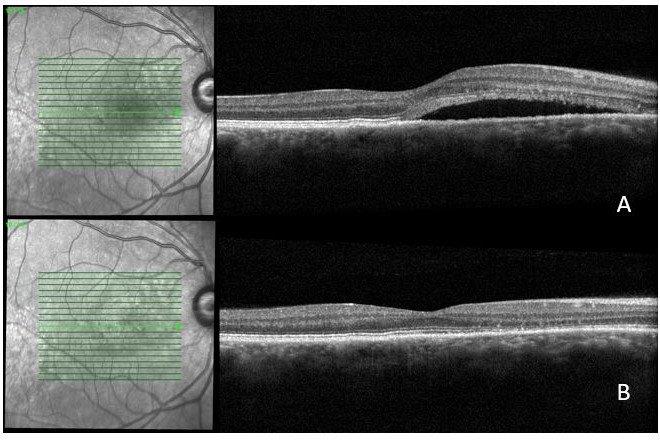

A 36-year-old man with vision loss in his right eye. His acuity was recorded at 6/21 right and 6/6 left. Examination and OCT showed significant subretinal fluid in the right eye (Fig 3A), an area of fibrinous changes nasally and an associated pigment epithelium detachment. OCT angiography did not show any macula neovascular membrane. Over a four-month period of observation, the subretinal fluid decreased, but did not disappear (Fig 3B and C). A fluorescein angiogram confirmed ongoing leakage at the right nasal macula (Fig 4).

A gentle treatment with argon laser was performed (100mW, 10ms and 100µm). Six weeks after the laser therapy (Fig 3D), the condition has completely resolved, with a visual acuity of 6/9 in the right eye.